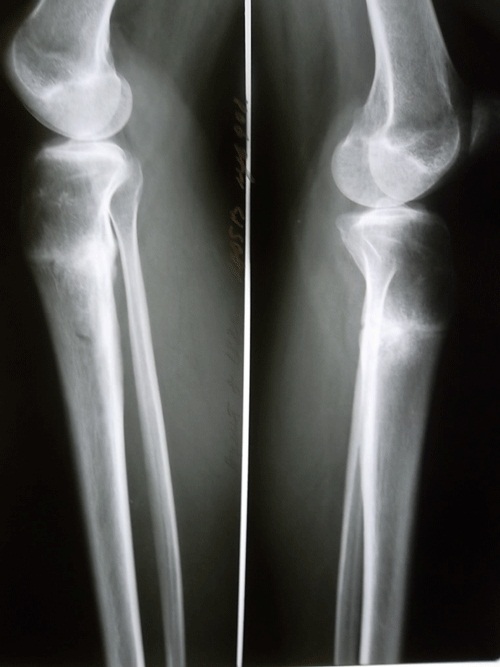

Рентген в 73 дня с момента снятия аппаратов.

Разрешены каблуки любых размеров! telka pusistiki